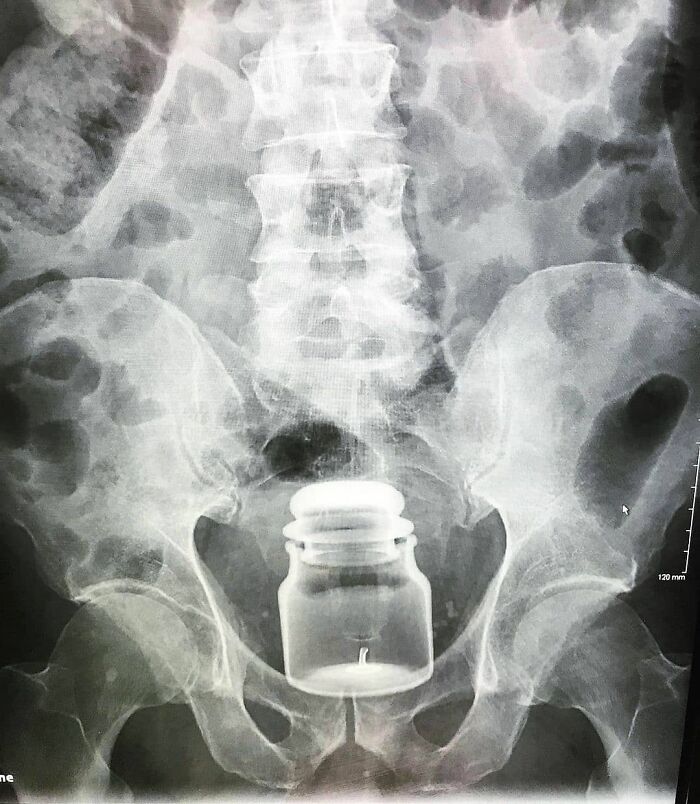

#65 Laparotomy Was Preformed To Remove The Foreign Body (Yankee Candle) Followed By A Temporary Colostomy

Image credits: medicalpedia